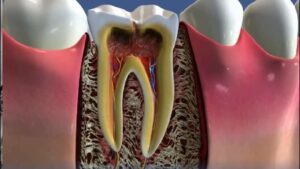

Ενδοδοντική θεραπεία – Απονεύρωση

Η ενδοδοντική θεραπεία και η απονεύρωση είναι δύο διαδικασίες που συνδέονται με την αντιμετώπιση των δοντιών, συχνά όταν υπάρχουν προβλήματα στον ιστό του δοντιού ή στις ρίζες του. Ας δούμε κάθε διαδικασία ξεχωριστά:

- Ενδοδοντική θεραπεία (Ενδοδοντία): Η ενδοδοντική θεραπεία είναι μια διαδικασία που χρησιμοποιείται για την αντιμετώπιση των δοντιών που έχουν προβλήματα στον ιστό του δοντιού ή στις ρίζες του, συνήθως λόγω βαθιών καριές, περιοδοντικής νόσου, τραύματος ή άλλων παραγόντων. Τα βασικά βήματα περιλαμβάνουν:

- Εντοπισμός του προβλήματος: Ο οδοντίατρος αξιολογεί την κατάσταση του δοντιού χρησιμοποιώντας ακτινογραφίες και κλινική εξέταση.

- Αναισθησία: Εφαρμόζεται τοπική αναισθησία για την αναισθητοποίηση της περιοχής.

- Αφαίρεση του ιστού του δοντιού: Ο οδοντίατρος αφαιρεί τον πληγέντα ιστό του δοντιού και των ριζών του.

- Ενδοδοντική επεξεργασία: Οι ρίζες του δοντιού καθαρίζονται, σχηματίζονται και γεμίζονται με ειδικό υλικό για να αποτραπεί η περαιτέρω μόλυνση.

- Κλείσιμο: Μετά την ενδοδοντική επεξεργασία, το δόντι κλείνει με σφράγισμα.

- Απονεύρωση (Οδοντική Απονεύρωση): Η απονεύρωση είναι μια προχωρημένη ενδοδοντική θεραπεία που εφαρμόζεται όταν ο ιστός του δοντιού έχει περαιτέρω καταστραφεί και η απονεύρωση του δοντιού αποτελεί την μοναδική επιλογή για τη διατήρηση του. Τα βήματα περιλαμβάνουν:

- Εντοπισμός του προβλήματος: Ο οδοντίατρος αξιολογεί την σοβαρότητα του προβλήματος και καθορίζει αν απαιτείται απονεύρωση.

- Αφαίρεση των ριζών: Οι ρίζες του δοντιού αφαιρούνται πλήρως.

- Απονεύρωση: Ο οδοντίατρος τοποθετεί μια τεχνητή ρίζα και στη συνέχεια τον τεχνητό δόντι.

- Ολοκλήρωση: Μετά την απονεύρωση, το δόντι είναι σχεδόν όμοιο με τον φυσικό δόντι.

Οι δύο αυτές διαδικασίες χρησιμοποιούνται για να διατηρήσουν τη δοντική υγεία όταν οι δόντια παρουσιάζουν σοβαρά προβλήματα στον ιστό τους ή στις ρίζες τους. Είναι σημαντικό να συζητήσετε με τον οδοντίατρό σας για τις επιλογές θεραπείας που είναι κατάλληλες για την περίπτωσή σας.